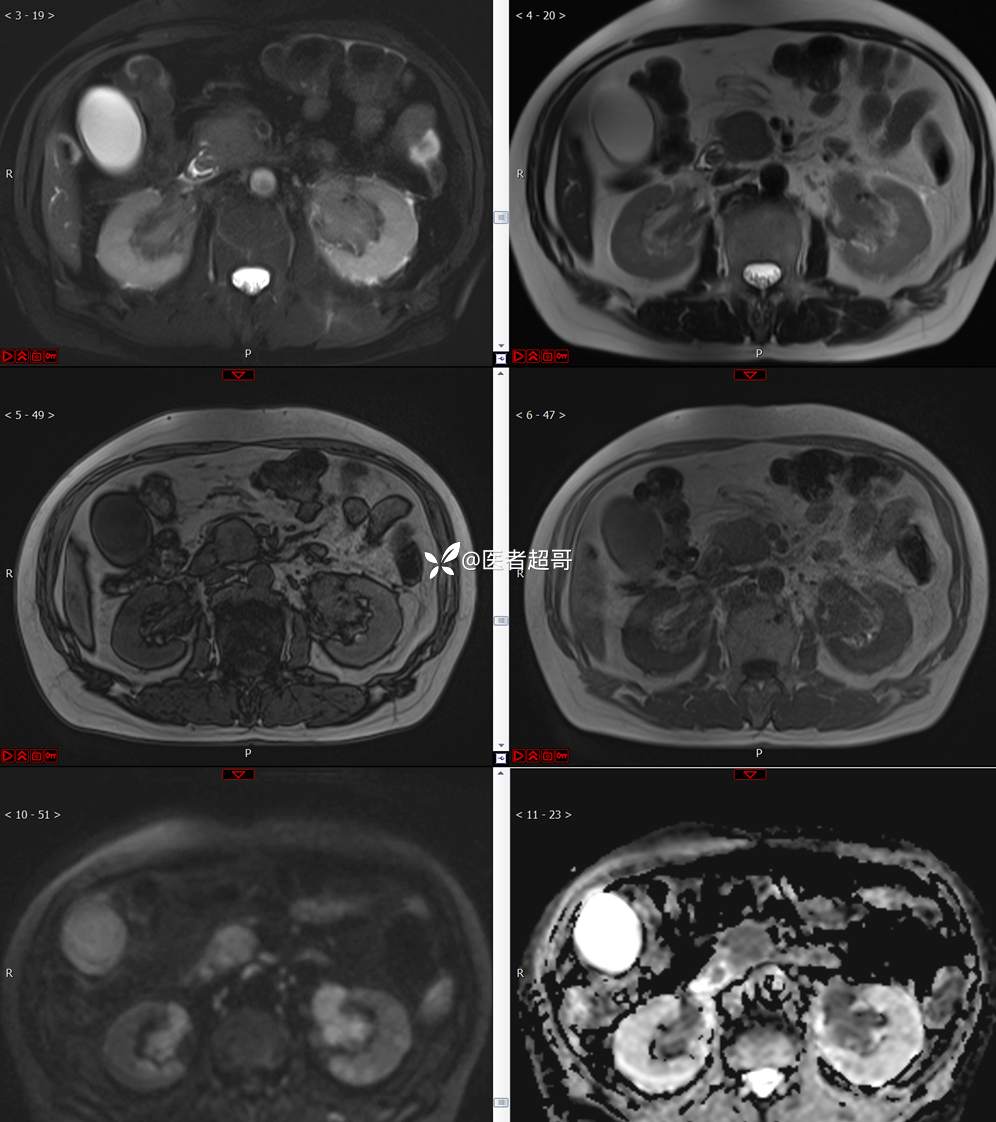

【影诊笔记772】腹痛就诊,发现肾脏病变,CT、MRI齐全,请高诊!

男,63岁 0200825 01

主 诉:间断腹痛15天

现病史:患者15天前无明显原因及诱因出现腹部疼痛不适,呈间断性钝痛,右下腹为著,无尿频、尿急、尿不尽,无发热、寒战,无腹胀。于市中心卫生院住院治疗,超声示:胰头低回声包块,胆系扩张,左肾囊肿,胆囊壁毛糙,胆囊内胆汁淤积。患者为求进一步诊治,遂以“肾盂肿瘤”收入院,患者自发病以来,神志清,精神可,饮食睡眠可,大便无明显异常,近期体重无明显增减。

既往史:既往体健